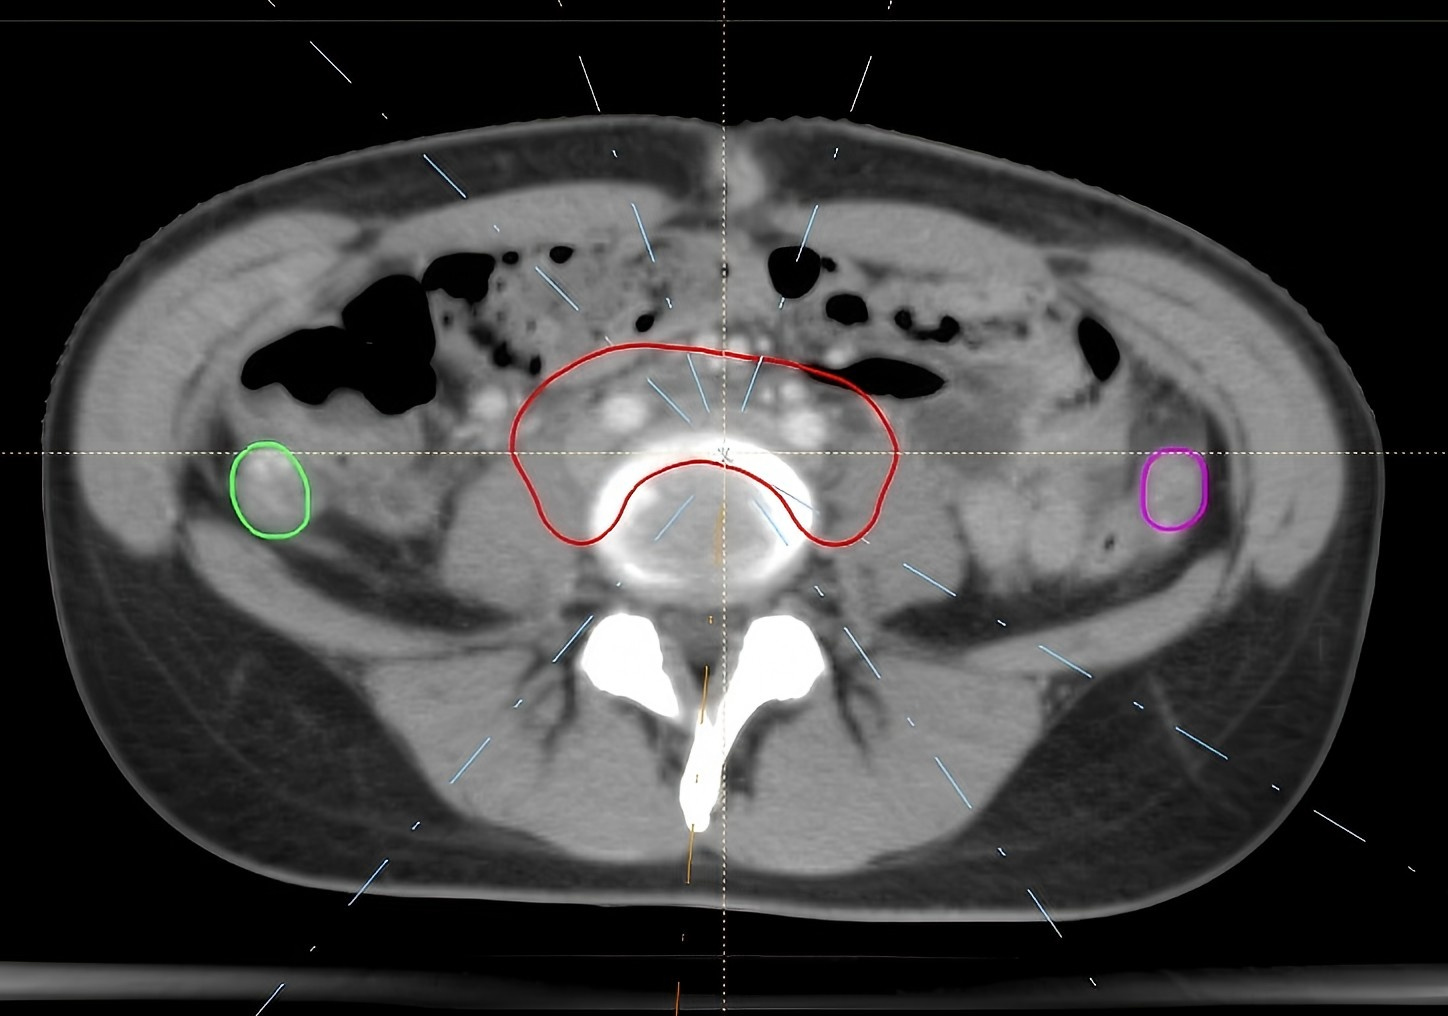

This study involved a comprehensive analysis of literature from 2015 to 2024 on ovarian function preservation during radiotherapy for cervical cancer, to identify technical trends. Additionally, patient data from Zhejiang Cancer Hospital from 2011 to 2018 was collected, focusing on patients who underwent radiotherapy to preserve ovarian function. Specifically, data from 10 patients with IA–IIB stage cervical cancer who underwent bilateral ovarian transposition (OT) and radiotherapy at our hospital between 2016 and 2018 was analyzed. Intensity-modulated radiation therapy (IMRT), volumetric modulated arc therapy (VMAT), and helical tomotherapy (HT) radiotherapy plans will be design for these patients to evaluate strategies for optimal ovarian protection. The optimal radiotherapy plan was determined through comparisons of dosimetric parameters.

(1) A literature review indicated that only 24 detailed reports on ovarian protection during cervical cancer radiotherapy have been published in the past 10 years. It has been established that ovarian protection presents a positive significance for cervical cancer patients, with OT being a necessary condition. Nevertheless, no standardized unified dose limit for ovarian radiation has been established. (2) After screening, a total of 77 patients with complete follow-up data from 2011 to 2018 were selected for the study. Following serum hormone level tests, 73 patients presented normal ovarian function prior to radiotherapy, while 4 demonstrated signs of impaired function. Three months after radiotherapy, 26 patients maintained normal ovarian function, 13 exhibited impaired function, and 38 showed a decline in function. One year later, 45 patients maintained normal ovarian function, 13 had impaired function, and 19 experiences further deteriorated function. The overall success rate amounted to 75.3%, and favorable clinical outcomes were observed. (3) Compared to IMRT and VMAT, HT reduced the maximum dose (Dmax) of the right ovary and demonstrated dosimetric advantages in terms of Dmax of the planning target volume (PTV), as well as in 30 Gy (V30) and 40 Gy (V40) of the bladder, and Dmax of the spinal cord. These differences were statistically significant. Compared with HT, IMRT and VMAT had advantages in the minimum dose (Dmin) of PTV and the mean dose (Dmean) of the left femoral head, and the differences were statistically significant. Compared with VMAT, most dosimetric results of IMRT were similar and the differences were not statistically significant, but IMRT had an advantage in the conformity index (CI) of PTV (p = 0.016).

Following receiving a certain radiation dose, the ovaries may undergo a temporary functional decline or even complete failure. The key to protecting the ovarian function during cervical cancer radiotherapy lies in successful OT, precise delineation of ovarian tissue, determination of dose limits for patients across different age groups, as well as the application of HT and specialized IMRT techniques.